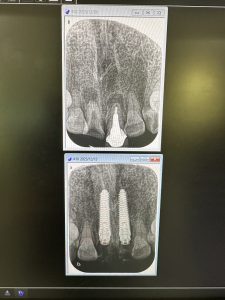

径3.5 長さ18ミリ、径4.0 長さ18ミリ

ISQ80台、ITV70〜80台👍

6〰️8w後には印象だ💪

いつもフリーハンドだが、ドンビシャ!

顎骨形態が脳みそに染みこんでるからね

便利なCTソフト見てるからイメージが湧く